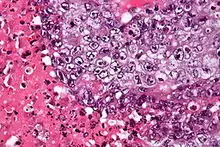

| Micrograph of an embryonal carcinoma showing its typical features – prominent nucleoli, marked nuclear atypia, necrosis, and nuclear overlap. H&E stain. | |

The microscopic features include: indistinct cell borders, mitoses, a variable architecture (tubulopapillary, glandular, solid, embryoid bodies – ball of cells surrounded by empty space on three sides), nuclear overlap, and necrosis.